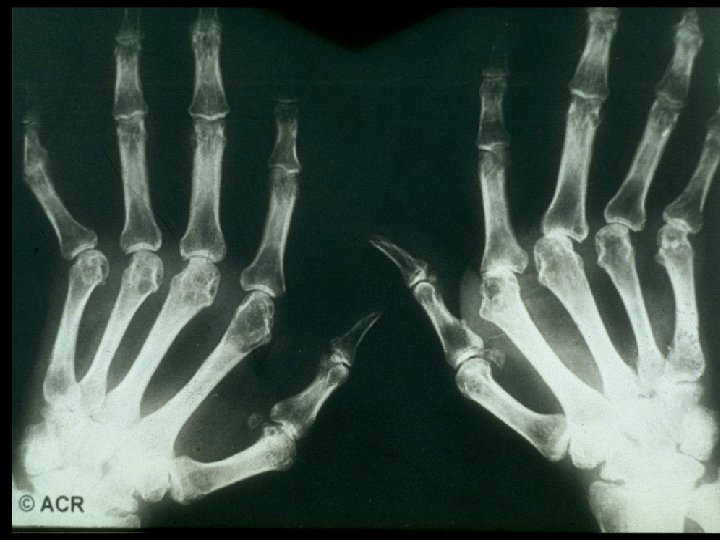

· On exam, he showed signs of extensive rheumatoid arthritis, most marked on hand, foot, and shoulder joints as well as rheumatic nodules on both elbows. · HR regular at 105/min · BP 130/90 mm Hg · ESR 82 mm/h

Rheumatoid Arthritis - A systemic, inflammatory polyarthritis that leads to joint destruction, deformity, and loss of function - Several potentially severe extra-articular manifestations - Pathology of RA involves the synovial membranes and periarticular structures of multiple joints, resulting in: - Pain - Swelling - Stiffness - Uncontrolled inflammation that can lead to irreversible damage and deformity - Functional limitation ACR Subcommittee on RA Guidelines. Arthritis Rheum. 2002; 46: 328– 346; Goronzy JJ, Weyand CM. In: Klippel JH, et al, eds. Primer on the Rheumatic Diseases. 12 th ed. Atlanta, GA: Arthritis Foundation; 2001: 209– 217; Anderson I. 2 RJ. ibid. 218– 225; Arnett FC, et al. Arthritis Rheum. 1988; 31: 315– 324.

Baseline Evaluation of Patients · Physical Examination - Documentation of actively inflamed joints - Documentation of mechanical joint problems: loss of motion, crepitus, instability, deformity - Documentation of extra-articular manifestations - Optho, cardiac, pulmonary, rash, LAD

Prognostic Markers in RA · Definitive Markers - Subcutaneous nodules - Detection of erosions on x-ray

Joint Erosions Occur Early in RA Maximum % Joints Affected · Up to 93% of patients with <2 years of RA may have radiographic abnormalities · Erosions can be detected by MRI within 4 months of RA onset Hand MTP All · Rate of progression is significantly more rapid in the first year than in the second and third years Year Fuchs HA et al. J Rheumatol. 1989; 16: 585 -591. Mc. Queen FM et al. Ann Rheum Dis. 1998; 57: 350 -356. van der Heijde DM et al. J Rheumatol. 1995; 22: 1792 -1796.